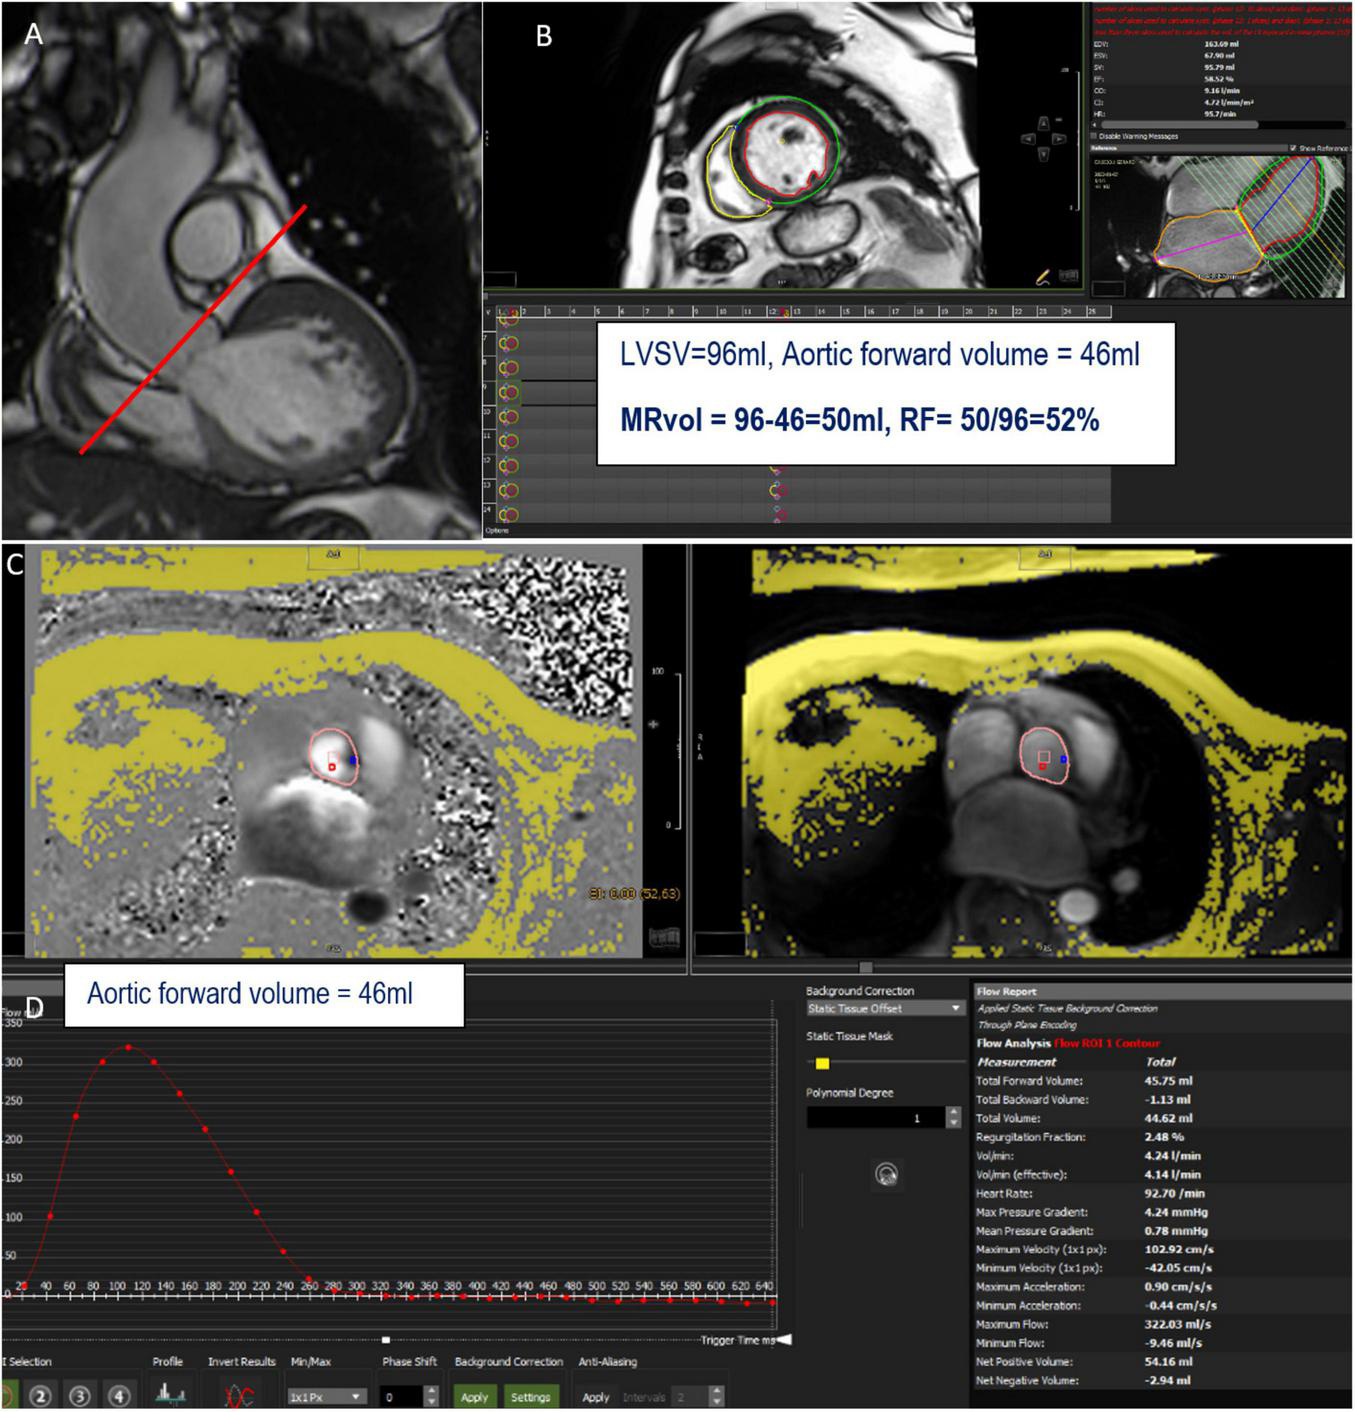

FIGURE 2

Example of mitral regurgitation (MR) assessment using indirect method n°1. LVOT bSSFP images show the perpendicular line above the aortic valve (red line) indicating the slice position for phase-contrast velocity mapping (A). Assessment of left ventricular stroke volume (LVSV) from short-axis cine SSFP images (B). Phase and magnitude images with delineation of the aorta (C) generating flow curves (D). This patient has a severe MR with a mitral regurgitant volume (MRvol) of 50 ml and a regurgitant fraction (RF) of 52%.